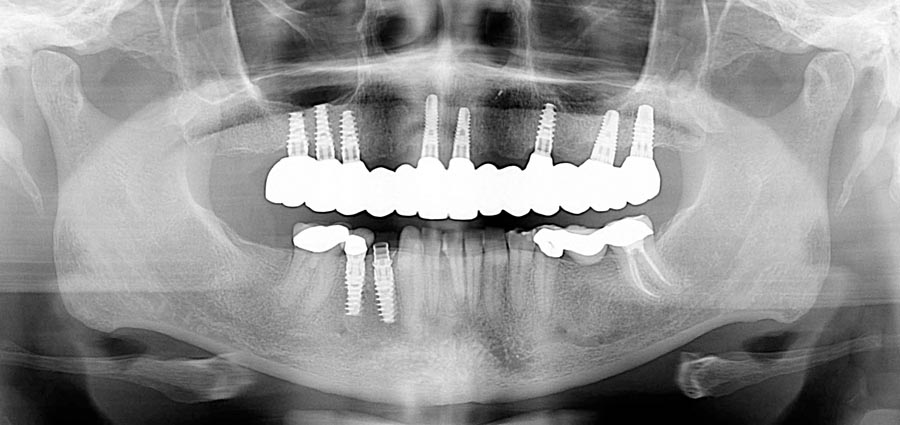

Smile GalleryImplant RestorationsFull Mouth Implant Restoration Full arch zirconia implant bridge (full smile) 1 of 37 Pre-op full smile Pre-op lips retracted Pre-op panoramic x-ray Extraction of strategic teeth Placement of implants Extraction of some remaining teeth after verification of adequate implant stability Occlusal view Post-op panoramic x-ray Immediately fabricated provisional restoration (tissue side view) Immediately fabricated provisional restoration (occlusal side view) Immediate provisional delivered on day of surgery Immediate provisional 2 weeks later Scalloped tissue developed from the provisional at 2 weeks Jig used for making a master impression Provisional in place (full smile) Provisional in place (lips retracted) Provisional in place (right side) Provisional in place (left side) Wax try-in (full smile) Wax try-in (right side full smile) Wax try-in (left side full smile) Wax try-in (full face, lips together) Wax try-in (full smile) Wax try-in (right side) Wax try-in (left side) Wax try-in (lips retracted) Full arch zirconia implant bridge on master cast (frontal view) Full arch zirconia implant bridge on master cast (occlusal view) Implant positions and soft tissue representation on master cast (occlusal view) Soft tissue representation on master cast (frontal view) Full arch zirconia implant bridge (tissue side view) Soft tissues on day of delivery (occlusal view) Soft tissues on day of delivery (frontal view) Full arch zirconia implant bridge delivered (lips retracted) Full arch zirconia implant bridge (lips retracted, close up) Post treatment panoramic x-ray Full arch zirconia implant bridge (full smile)